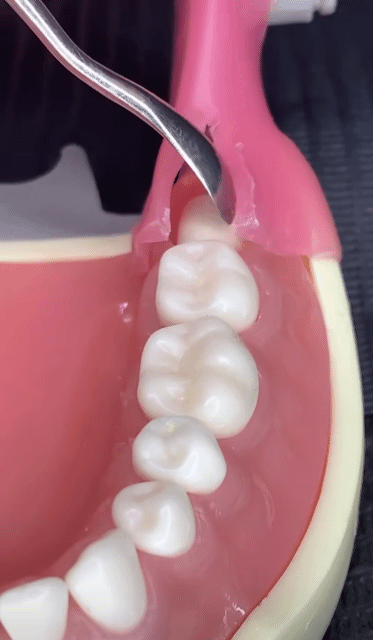

매복사랑니 발치법

닉네임또리비니등록 날짜&시간2024.01.09

ㄷㄷㄷ